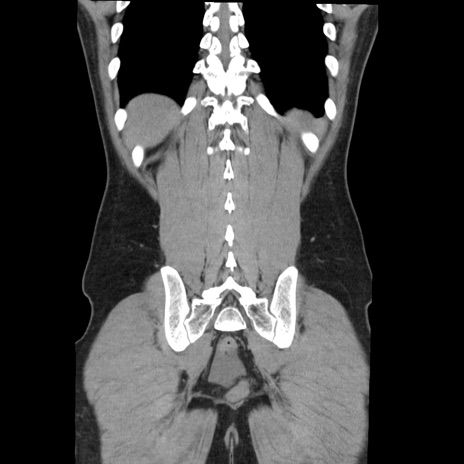

症例36(冠状断像)

【症例】20歳代 男性

【主訴】心窩部痛

【現病歴】今朝より上腹部痛あり。一旦軽快していたが再度出現したため救急要請。昨日夕に白身の魚を含む刺身を食べた。

【身体所見】BP 136/89mmHg、HR 74/min、BT 37.0℃、腹部:膨満、軟、心窩部に圧痛あり。反跳痛なし、筋性防御なし、腸雑音やや亢進あり。

【データ】WBC 17700、CRP 0.48